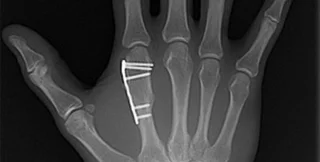

Перед тем, как изготавливать искусственную кость медикам будет нужно сделать рентгеновский снимок и томограмму поврежденного участка, чтобы в дальнейшем система изготовления костной ткани могла в точности воспроизвести размеры и форму поврежденной кости. Сообщается, что технология производства способна производить кости довольно замысловатой формы, например, челюсти или фрагменты черепа. Минимальная толщина искусственной кости составляет 1 мм, что более чем достаточно для подавляющего большинства костей в организме.